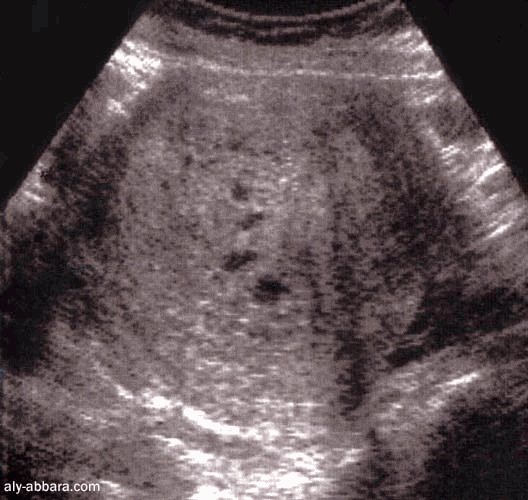

Grossesse môlaire (môle hydatiforme)

- aspect échographique et virtuel -

Coupe transversale sur l'utérus